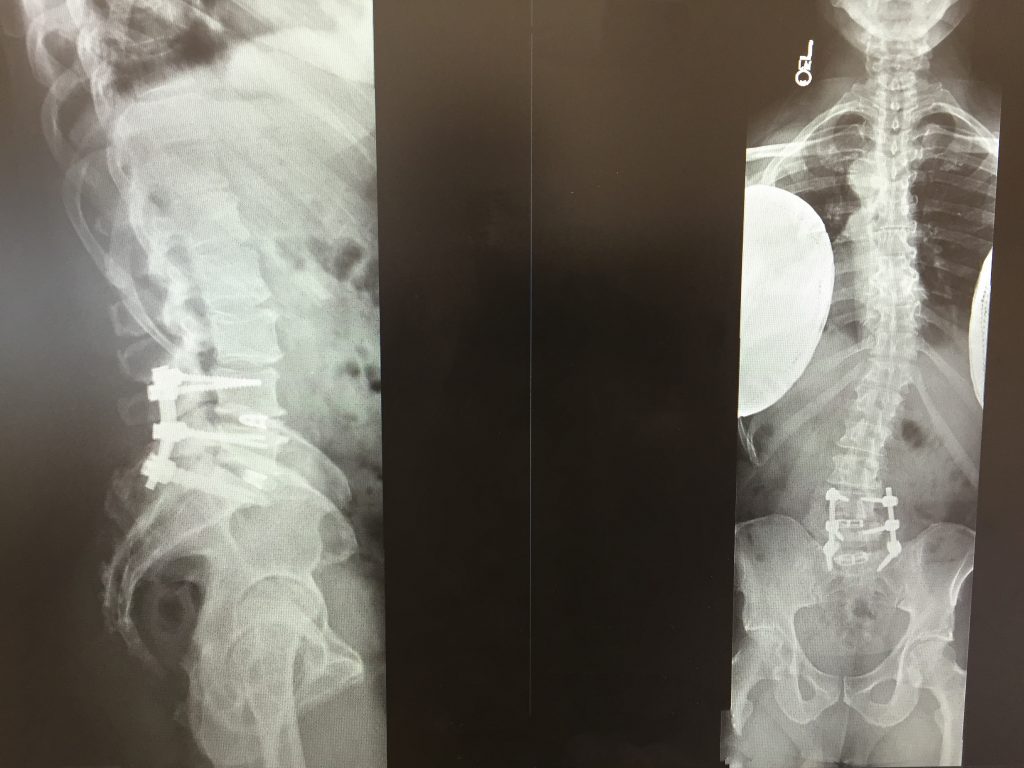

Patient image of: Kenneth Lucas

First I'd like to Thank Dr. Han Jo Kim for his professional advice and calm demeanor as well as the amazing team at HSS. I suffered from 2012 up until I had my surgery in March 2019 with constant unbearable pain throughout both my legs. Unable to perform simple task resulted in losing my job. I had lost hope and figure pain medication would be my solution. July 2018 is when all that changed. I paid a visit to a local facility for epidural injections (This would have been my 9th injection since 2015). After viewing my MRI his first suggestion was obvious - I would need spinal fusion due to the nerves were obstructed from multiple disc herniations at S1, L4, and L5 along with scoliosis. My physician gave me a list of surgeons and his recommendation was Dr. Kim all due to his successful record. I thank God I went in 100% believing this would be the answer to all my pain suffering. My surgery was a success! The procedure (posterior lumbar decompression L5, fusion L4-S1, TLIF L4- S1) took 3 hours. I was home in 3 days! I must add, the pain was minimal with the aide of extra strength pain relievers only. The entire staff during the 3 days were excellent never worried nor negative. Gasby was one of the nurse assistants I favored the most. He was always super upbeat, kind and had a great sense of humor. Even the food was restaurant quality (I was dismissed on the evening that serves meatloaf). I highly recommend HSS to everyone!